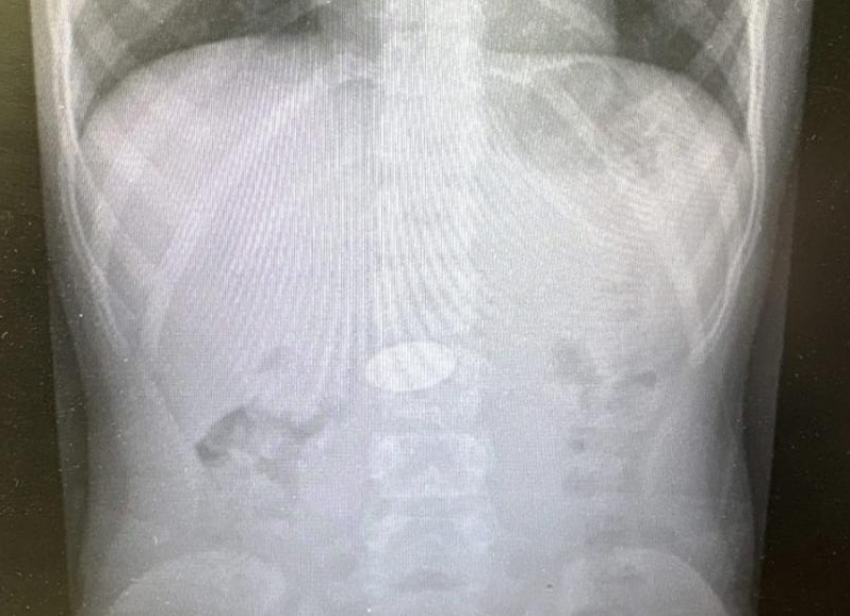

В Волгограде хирурги извлекли из желудка ребенка 5 рублей

Фото: Облздрав

Волгоградские врачи детской больницы №7 провели экстренную операцию малышу, который умудрился проглотить крупную монету. Железный «рубль» застрял в желудке ребенка. К счастью, медицинское вмешательство прошло успешно — сейчас он уже дома и чувствует себя хорошо. Однако этот случай заставил хирургов вновь обратиться ко всем родителям с отчаянным предупреждением.